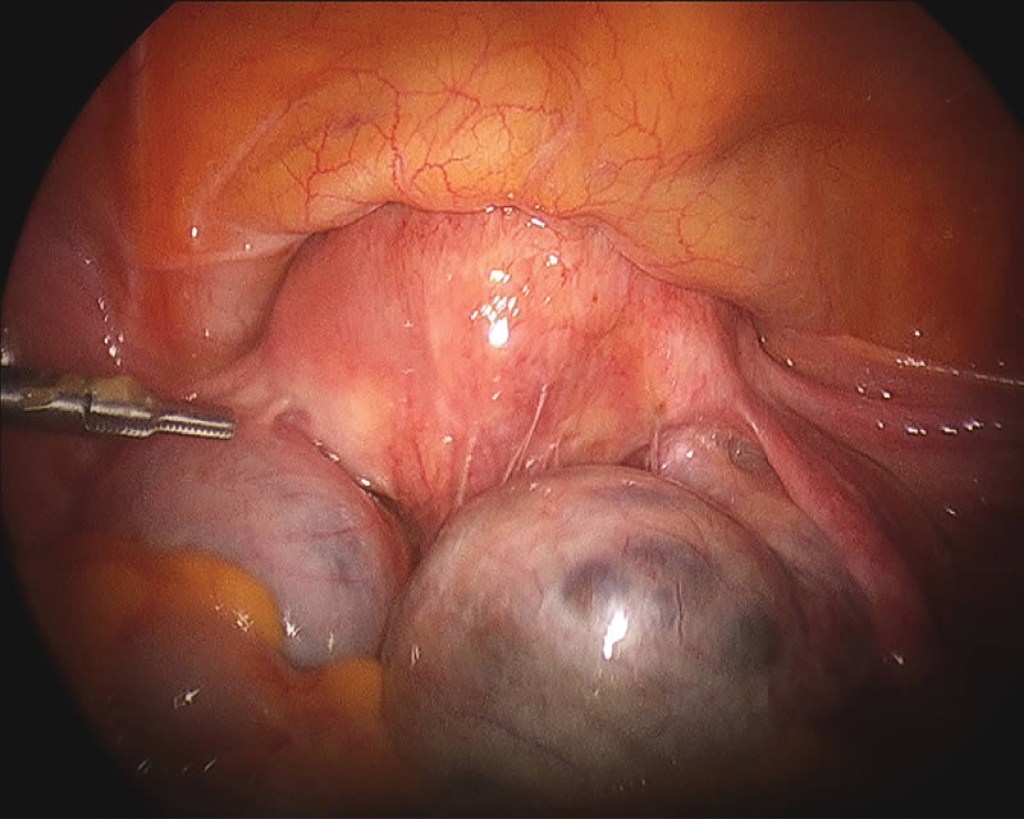

A sample of the tumour’s tissue is the only definitive way a brain tumour can be diagnosed. A sample of tumour tissue for examination under a microscope by a pathologist, a doctor who specialises in interpreting laboratory tests and evaluating cells, tissues, and organs to diagnose disease. A biopsy can be done as part of surgery to remove the entire tumour. Or surgery may be done as a separate procedure if completely removing the tumour is not possible because of its location or a patient’s health.